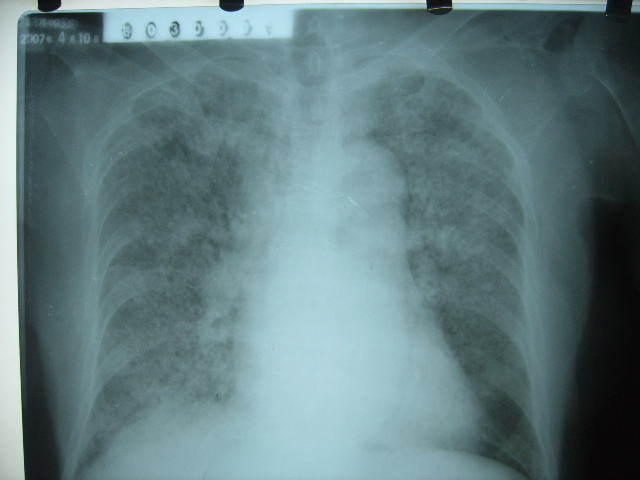

女 79岁,今日高烧,无咳嗽及痰,是否粟粒结核还是?

双肺弥漫性病变,以肺间质改变为主,

1特发性肺间质纤维化2结节病3过敏性肺炎4淋巴管播散癌.需结合临床.

胸内小结节部分融合成片,边缘模糊,

考虑肺部特殊感染-霉菌?建议痰培养。

双肺弥漫小结节状高密度,部分融合,边界不清(因为不是hrct,可能为部分容积效应引起),肺门纵隔内未见肿大淋巴结影。无胸腔积液。

考虑:急性血型播散型肺结核,不除外过敏性肺炎;建议治疗后复查。

双肺弥漫性结节影,双肺上叶为著.纵隔内可见一肿大淋巴结影,密度较高.支持急性血行播散型肺结核.双侧少量胸腔积液.

双肺弥漫基本均匀分布的小结节状高密度影,部分融合。支持急性血性播散性肺结核。

两肺弥漫分布小结节状高密度影,其大小,密度一致,分布均匀,并可见与后胸壁平行的弧状影

诊断:两肺急性血型播散形肺结核